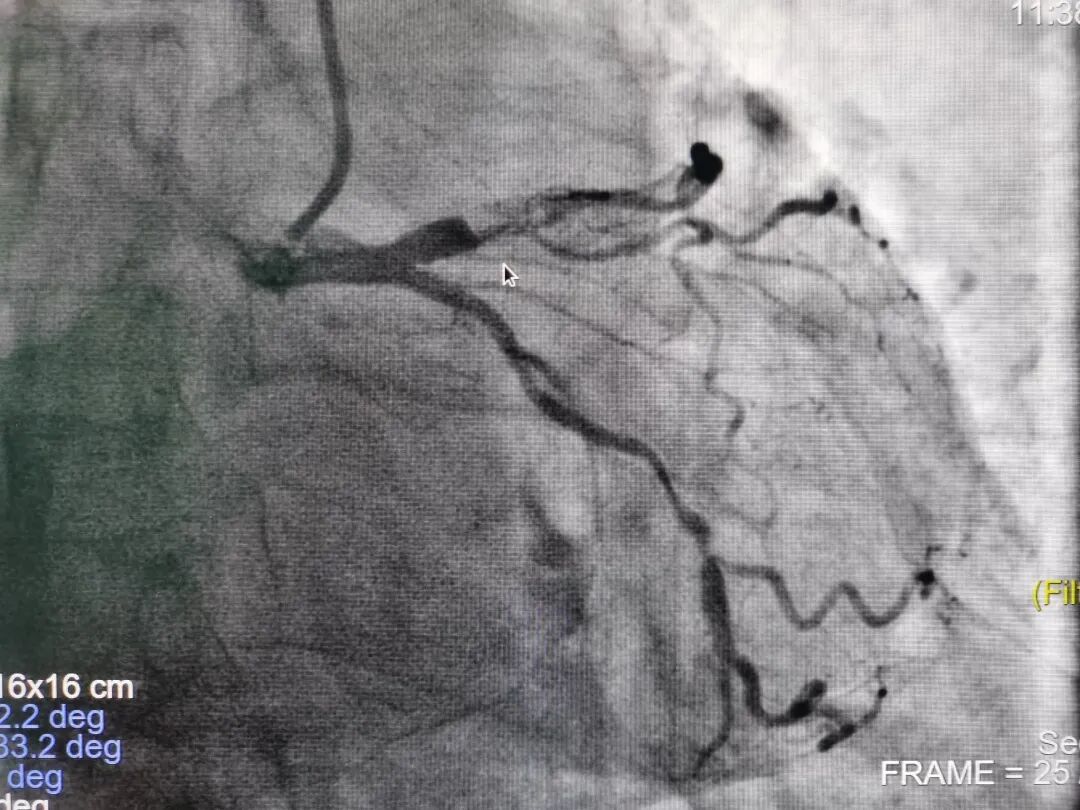

术前影像

据心内科廉哲勋主任介绍,病人是一位62岁的男性冠心病患者,外院造影显示冠状动脉左前降支近中段有弥漫、严重狭窄伴重度钙化及血管迂曲,从外院转入青大附院。经团队充分讨论后,在血管内超声评估和指导下,采用Shockwave冲击波球囊钙化斑块碎裂技术,精确冲击冠状动脉内膜和中膜下钙化病灶后,顺利植入支架。